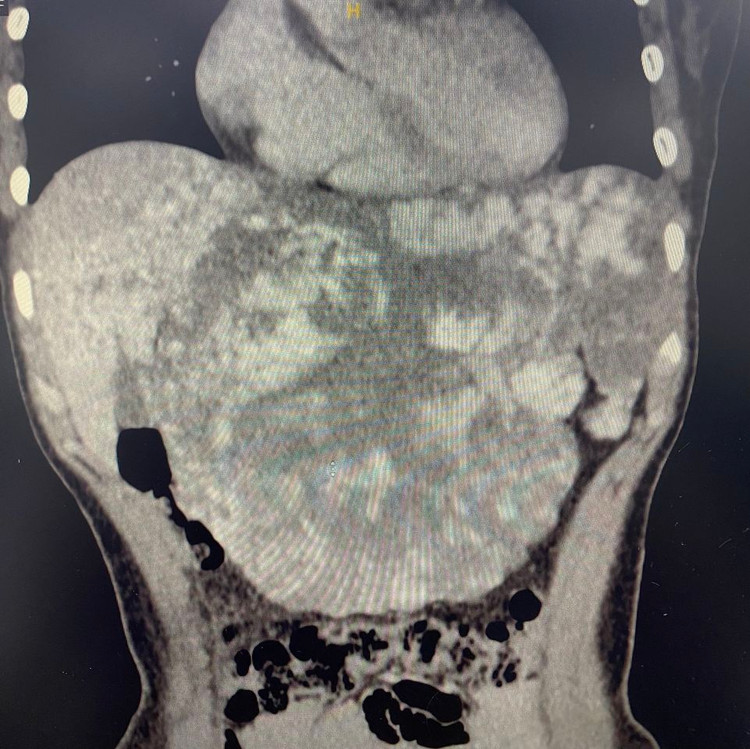

Theo lời kể của bệnh nhân N.T.H (46 tuổi, Thái Bình), thời gian gần đây bệnh nhân có biểu hiện đau tức bụng, ăn uống hay bị đầy tức bụng do khối u kích thước lớn chèn ép nhập viện trong tình trạng khối u chiếm gần hết khoang bụng. Sau khi thăm khám và thực hiện một số xét nghiệm cận lâm sàng, tại Khoa Phẫu thuật Gan Mật Tụy, Bệnh viện TWQĐ 108 các bác sĩ chẩn đoán: U máu khổng lồ gan trái, kích thước gần 30 cm.

| Khối u máu gan khổng lồ trên phim chụp |